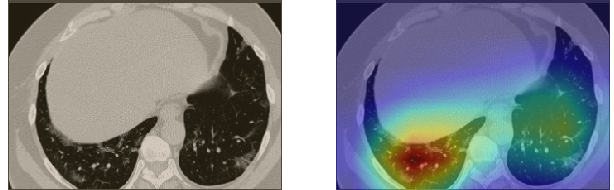

In order to make our models more transparent and provide detailed visual analysis, we present the Grad-CAM localization maps obtained by different models. We consider CT images with COVID-19 abnormalities from the test set of each dataset and highlight the important regions considered for the prediction. For the SARS-CoV-2 dataset we use the Inception V3 model. Figure 13 shows the original CT images and their localization maps. Our model is capable to detect regions that show abnormalities in the CT scans.

In a similar way, we consider classifying the test CT scans from the COVID-19 dataset by the DenseNet169 model and highlight the important regions considered for predictions. We present the original CT images and their localization maps in Figure 13. We can also see that our model is capable to detect the COVID-19 related regions as marked (small square in some images) by expert radiologists.

A wide variety of typical and atypical CT abnormalities have been reported for COVID-19 patients in various studies [58, 59]. So, we tested our models on external CT images extracted from these two publications as they feature typical findings of COVID-19 pneumonia marked by specialists. In order to make sure that not any of the extracted images are unintentionally included in our datasets, specifically the COVID19-CT dataset, we use the model trained on the SARS-CoV-2 dataset. First, the InceptionV3 model is employed to classify the extracted CT images. The model is able to correctly classify the given CT images as COVID-19. Second, in order to interpret the model’s generalization capabilities, we apply the Grad-CAM technique to visualize the regions of abnormalities that are considered. By assessing the different CT images in Figure 15, we can see that the model accurately localizes the disease-related regions. Even more interesting is the fact that the model ignores any specific marks in the images like letters and only localizes the COVID-19 related regions. These visual explanations show the success of our models to learn relevant, generic visual features related to COVID-19 and are capable to correctly classify CT images outside the datasets on which they are trained.

Figure 16 shows various CT scans where only one lung is visible. The CT scans are also extracted from the paper [58] and show different CT manifestations of COVID-19 pneumonia marked by red squares. The InceptionV3 model is capable to classify them correctly as COVID-19, although it is trained on CT scans where the entire lung is visible. Intriguingly, when applying Grad-CAM we can see that all regions of abnormalities are accurately localized. This also proves the potential of our model to detect COVID-19 abnormalities in CT images outside the dataset used for training.